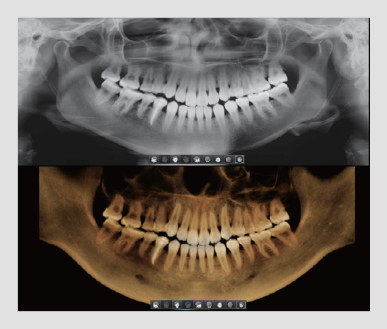

El innovador FOV proporciona un volumen en forma de arco que muestra una vista más amplia de la dentición en comparación con otros dispositivos del mismo FOV.

Normalmente, una imagen de 10x8.5 muestra el diente No.8. Sin embargo, cuando los terceros molares están tumbados sobre su lado hay una gran posibilidad de que el diente se corte de la imagen.

El “volumen en forma de arco” elimina esta posibilidad y muestra el área de dentición oculto.